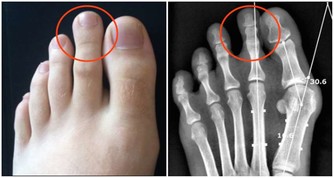

有著神奇的功效,對於治療中西醫束手無策的痛風,卻有令人無法想像的療效,只要早晚飲用一顆新鮮椰子水,即使痛風情況嚴重到骨關節變形,依然可以康復。 藥書泰斗嘉眾草師表示,根據統計發現,國人尿酸過高的情形日趨嚴重,而尿酸過高的患者極有會發展成痛風。 高尿酸的形成主要原因有二: 一、尿酸產生過多; 二、尿酸排泄減少。許多患者只有血清尿酸鹽濃度的增高而沒有臨床症狀,只有在發生關節炎時才稱為痛風。痛風的病理基礎是高尿酸血症,正常人血尿酸值是男性2.4-7mg/dL,女性1.6-5.2mg/dL。 當體液中尿酸濃度超過此值時,將因過剩而在組織中沈積,這種尿酸鹽的結晶沈積在關節滑膜、關節骨、軟骨而導致痛風性關節炎,沈積在皮下則形成痛風石。 中西醫均會要求痛風患者不可以攝取高普林食物,然而這些食物可以說是最起碼的美食,要痛風病患完全不吃這些食物,說真的,這種治療的犧牲代價還不小呢! 他們所提供的忌食食物包括有:雞、鴨、鵝、豬等內臟,以及魚、黃豆、發芽豆類、含酵母的飲料如養樂多、啤酒、豆苗、黃豆芽、蘆筍、紫菜、香菇、肉汁、濃肉湯、牛肉汁、雞精、酵母粉、健素糖等。 以上的食物對痛風患者來說,每一樣都必須忌口,那麼在飲食的享受上,他們都被排除在外,甚至平時可選擇的食物,必須去掉一大半以上,那麼人生還有什麼意義呢? 嘉眾草師以編著《小偏方治大病》、《草藥驗方大全》、《補酒藥酒大全》、《漢方治百病》、《癌症驗方大全》等等大部頭醫藥叢書聞名於世,他提供的驗方無不受到民眾的好評,為了對付中西醫束手無策的痛風,嘉眾草師特別介紹椰子食療法,患者只要每天飲用一至三粒新鮮椰子,一至兩個小時痛風就不再疼痛,連續飲用二至三個月,症狀即可消除。 如果沒有新鮮椰子,剝殼椰子也可以,每個約在廿至四十元之間。萬一購買不便,則改喝罐頭半天水、椰子水也可以,不過還是以新鮮椰子療效最好。 嘉眾草師表示,許多人耽心椰子會不會太涼?其實這是多慮了,因為患有痛風的人,本身體質會偏燥,高普林會不斷累積,椰子水正好可以清洗積存的痛風石,這是西藥秋水仙很難做到的。